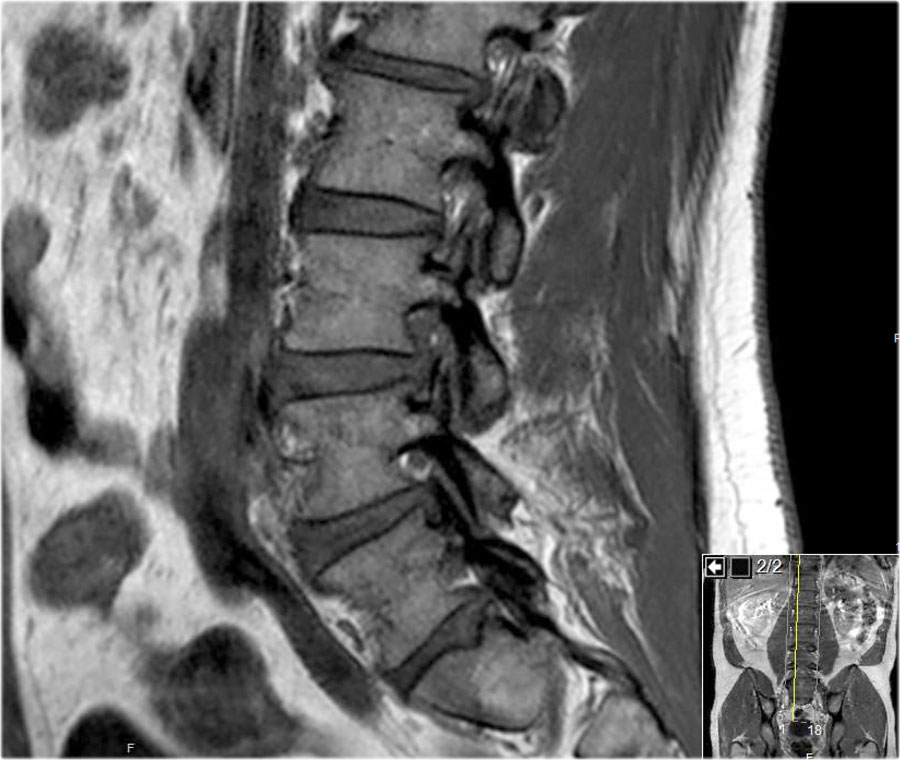

Hình ảnh chuỗi xung T1W mặt phẳng đứng dọc cho thấy một cấu trúc giảm tín hiệu rất thấp tại mức L4L5 (mũi tên) và tại mức L5S1.

Tiếp tục xem các hình ảnh chuỗi xung T2W.

Trên chuỗi xung T2W, cường độ tín hiệu cũng rất thấp.

Chụp CT được thực hiện để xác định liệu đây có phải là đĩa đệm thoát vị bị vôi hóa hay một xảo ảnh nào đó.

Tiếp tục xem các hình ảnh CT.

Tín hiệu thấp cuối cùng được giải thích là do hiện tượng chân không (vacuum phenomenon) gây ra bởi khí nitơ trong đĩa đệm thoát vị tại cả mức L4L5 (mũi tên đỏ) và mức L5S1 (mũi tên xanh dương).